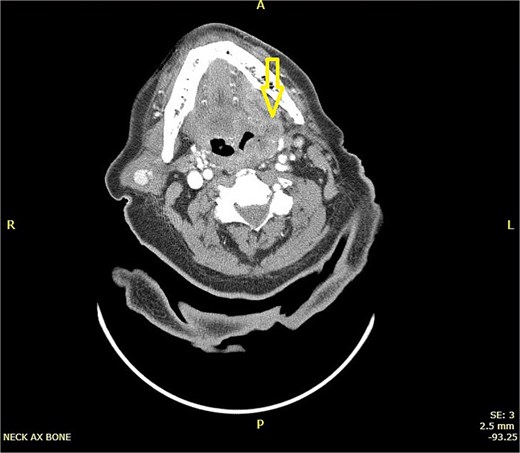

CT scan neck with contrast (Figs 1 and 2):

CT scan of neck showing a hyper-dense lesion in the tail of the right parotid gland measuring 1.3 × 0.9 cm (AP, TV dimensions) with no deep extension. The left tonsil is enlarged with faint, il-defined rim enhancement, and central air foci, indicating early abscess formation.

CT left parotid hyper-dense lesion, which may indicate lymph node metastasis or primary tumor. For pathological correlation (which showed Warthin tumor) and early left tonsillar abscess for clinical correlation.